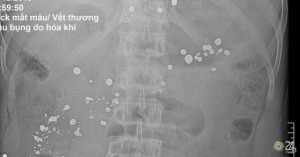

Người đàn ông bị thủng 15 lỗ ở dạ dày, sốc mất máu nhiều do gặp tai nạn bất ngờ từ súng tự chế.